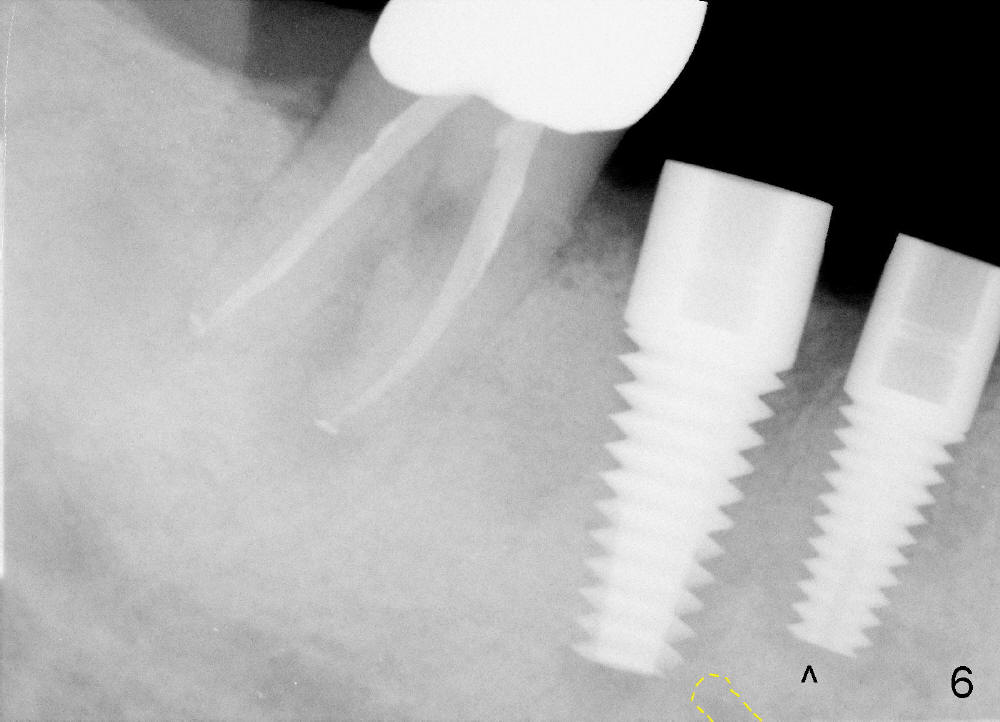

One month after implant placement at the sites of #29,30, the former is found loose (Fig.1,2). It is placed higher than #30. Three weeks later, PA is retaken to confirm that there is space apical to the implant at #29 (Fig.3 double arrows) and that there is distance from the mental loop (yellow dashed line). After infiltration anesthesia, the implant is torqued down initially (compare Fig.4,5) and more (Fig.6,7). To prevent re-loosening, the two implants are splinted (Fig.8).